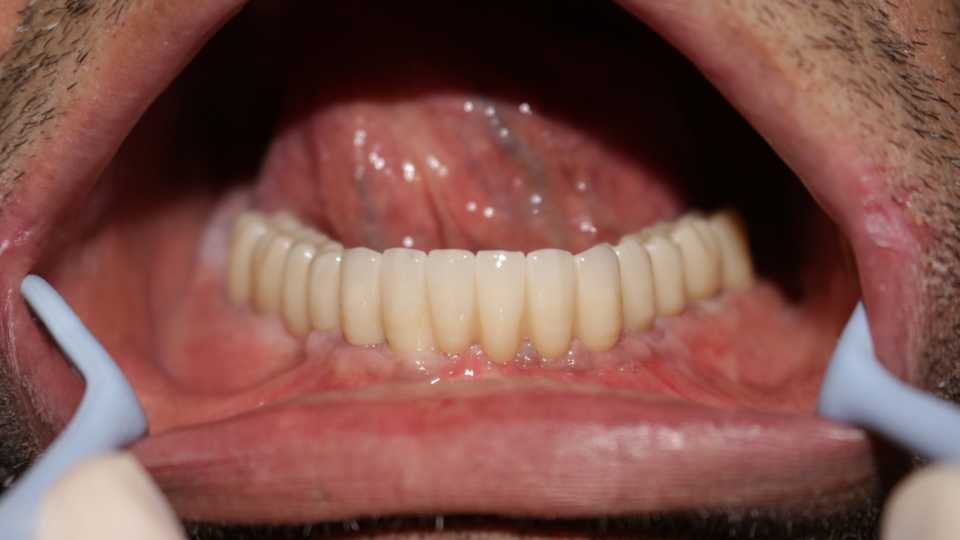

Reabilitare orală cu implanturi dentare Paltop, protezate cu lucrare insurubabila fixa din ceramica pe suport de zirconiu

Cazul 64: All on 6

A doua etapă – la aproximativ 5 săptămâni de la prima intervenție, implanturile sunt protezate printr-o lucrare fixă, înșurubabilă, din ceramică pe suport de zirconiu (preț: 1.500 lei per element).